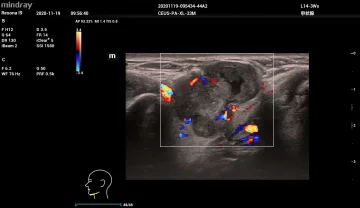

HR-flow™ режим отображения кровотока с высоким временным и пространственным разрешением для точной и однородной визуализации сосудов, в том числе самых мелких

Smart Doppler интеллектуальная оптимизация доплеровских режимов

Smart Track автоматическая подстройка расположения и угла наклона рамки цветового допплера с автоматическим отслеживанием положения контрольного объема

V-Mapping оконтурирование с сенсорного экрана зоны интереса в протоколах сосудистых исследований